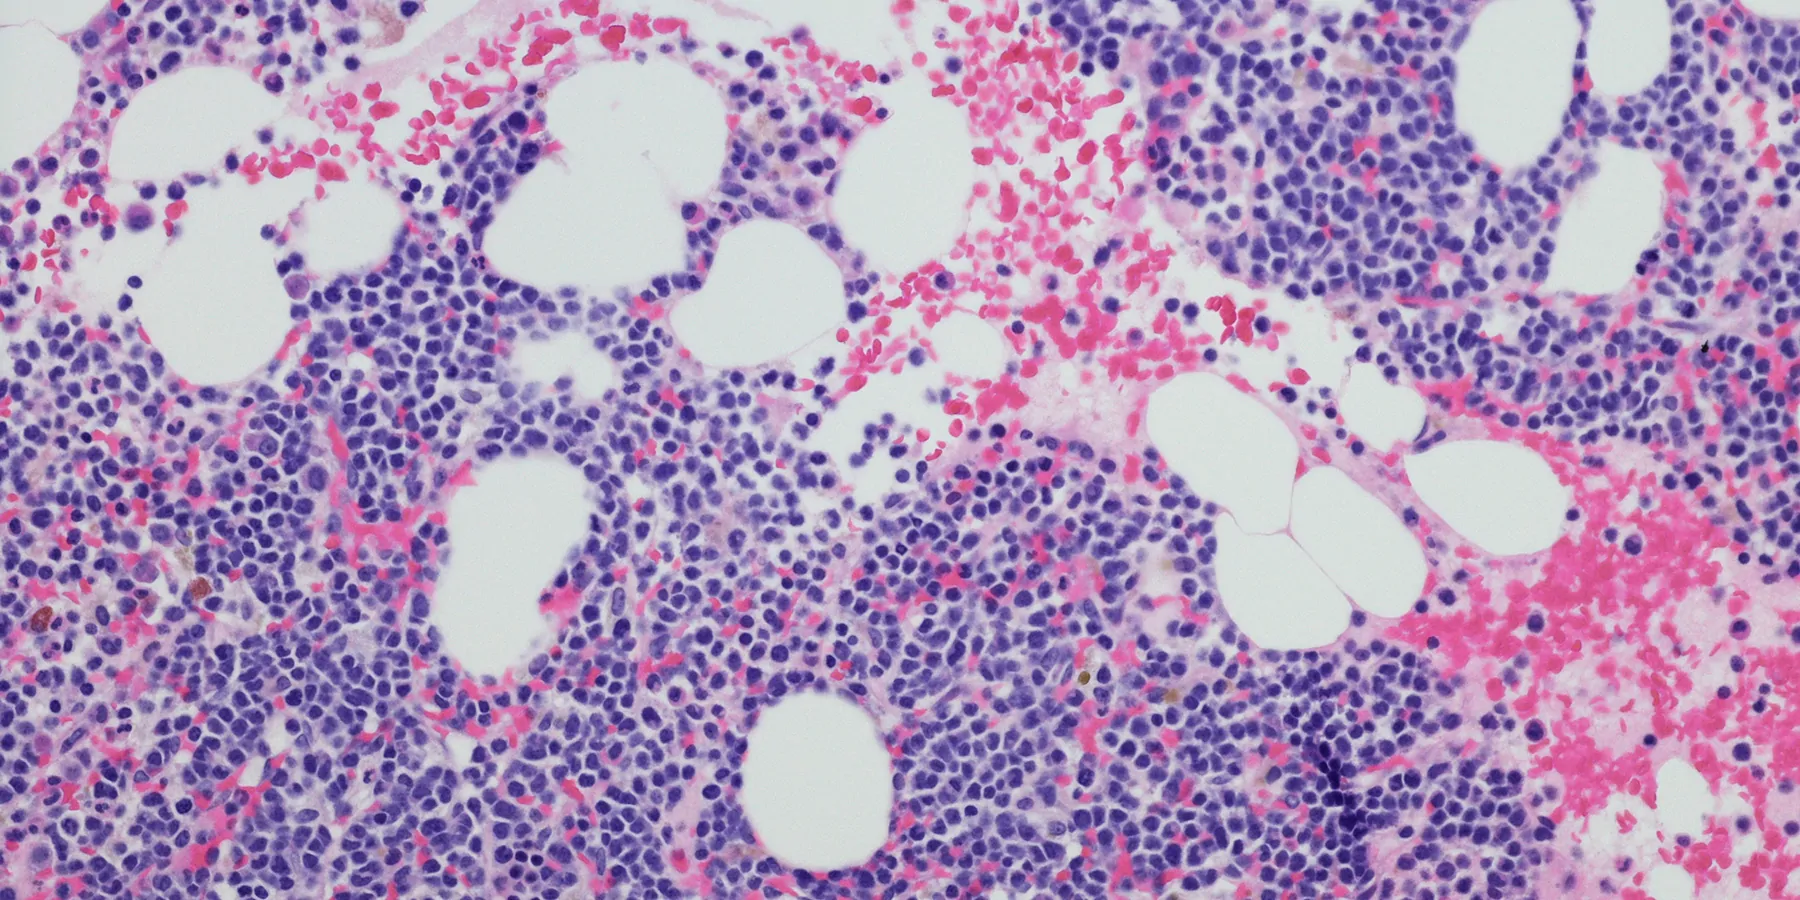

Researchers at Washington University School of Medicine in St. Louis, MO, have identified a key protein called dual-specificity phosphatase 6, or DUSP6, that drives the progression of leukemia from chronic to the aggressive stage. Their study in mice models has shown that blocking DUSP6 prevents myeloproliferative neoplasms (MPN) from aggravating into life-threatening secondary acute myeloid leukemia (sAML).

Patients with MPN and sAML are treated with anti-inflammatory therapy involving Janus-kinase (JAK2) inhibitors. When researchers analyzed the tumors of 40 patients treated with JAK2 inhibitors for MPN and sAML, all showed aberrantly high expression of the DUSP6 gene. Blocking DUSP6 helped overcome the resistance that leukemias often develop to JAK2 inhibitors, suggesting DUSP6 plays a pivotal role in mitigating the severity of leukemia.